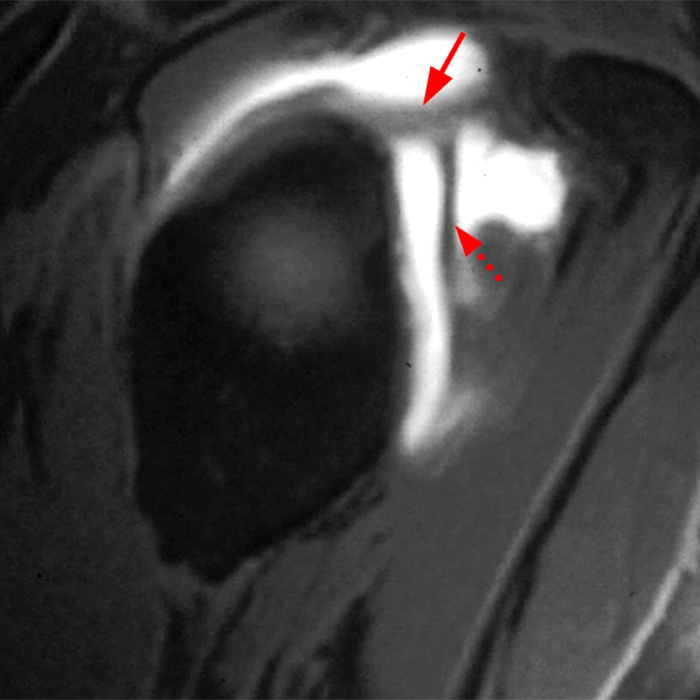

![]() |

L'SGHL è costituito da fibre dirette e oblique, decorre dal labbro glenoideo e/o dal tubercolo sopraglenoideo in direzione laterale e si attacca alla fovea capitis della testa omerale, che è una piccola depressione della superficie articolare omerale appena sopra il piccola tuberosità. L'SGHL si attacca anche al solco bicipitale, alla parte superiore della piccola tuberosità e al tendine sottoscapolare, nonché al legamento trasverso dell'omero, contribuendo ulteriormente alla stabilità del tendine della testa lunga del bicipite. Esistono molte varianti dell'SGHL, tuttavia, con possibili inserzioni al tendine del bicipite stesso (sopra a sinistra in immagine assiale; freccia grossa SGHL, freccia piccola CLB) o alla porzione anteriore del labbro, oppure l'SGHL può presentarsi in comune con il legamento gleno-omerale medio ( sopra a destra immagine RM sagittale; freccia superiore SGHL).